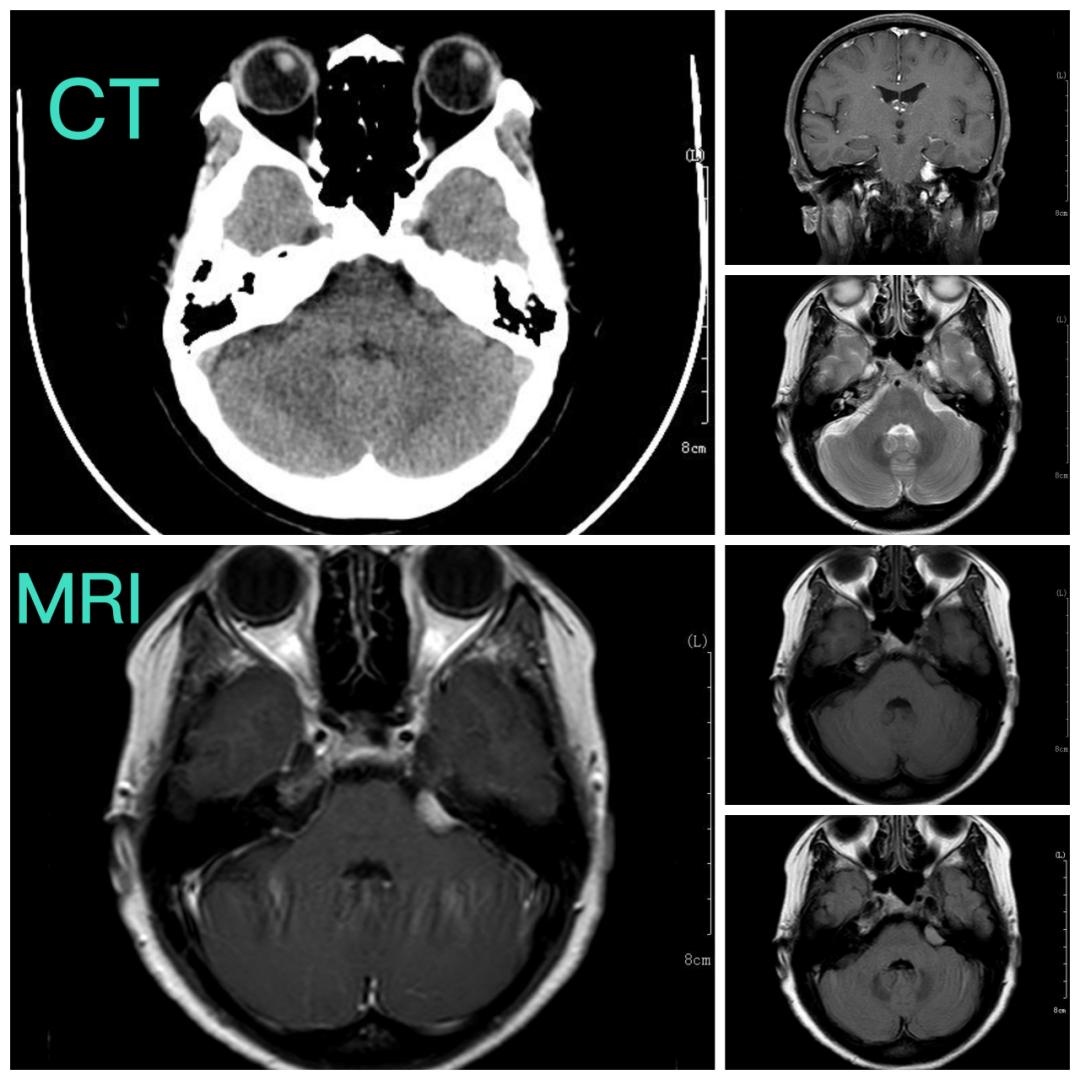

术前影像资料

张永力院长、神外二病区杨海峰主任、主治医师段磊认真询问患者病史及仔细查看患者影像资料,考虑肿瘤是脑膜瘤,位于左侧岩骨后壁,位置毗邻脑干和小脑,这个区域有很多脑神经出入,非常凶险,万幸的是肿瘤还比较小,需要尽早手术切除,以免肿瘤长大,增大手术难度,破坏脑干、小脑及脑神经功能,造成无法挽回的损伤。

患者目前右面部的麻木症状,考虑与脑瘤无明显关系,手术无法缓解右面部麻木症状,术后患者头痛症状可能会缓解,最重要的是可以完全切除肿瘤,避免以后对患者造成生命威胁。通过核磁共振影像,可以看出,肿瘤位于左侧岩骨后壁,与面听神经关系最为紧密,肿瘤虽小,但位置较深,经过术前讨论与研判,杨海峰主任认为,手术方式可以选择经神经内镜切除肿瘤,充分发挥神经内镜的优势,微创切口,深入抵达肿瘤所在部位,视野清晰,操作精准,在完整切除肿瘤的同时,完整保护面听神经及脑干、小脑等重要的结构。